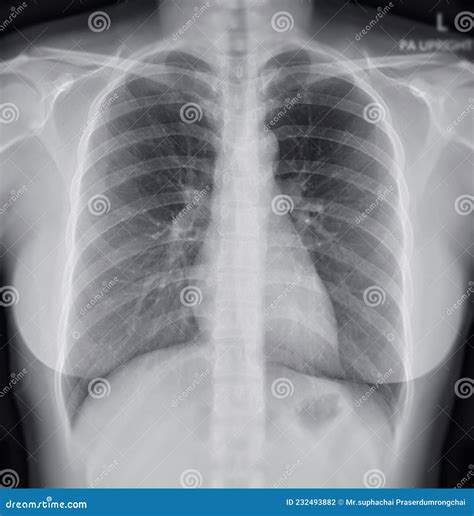

What Does a Normal Lung X-ray Look Like?

A normal lung X-ray typically shows clear lung fields with no signs of inflammation, infection, or other abnormalities. The lungs appear black due to the air they contain, while the heart and other structures appear white. The diaphragm, the muscle that separates the chest from the abdomen, is also visible and should be at a normal level.

Here are some key features of a normal lung X-ray:

• Clear lung fields with no opacities or infiltrates.

• Normal heart size and shape.

• Visible costophrenic angles (the angles where the ribs meet the diaphragm).

• No pleural effusions (fluid accumulation around the lungs).

• Normal vascular markings.